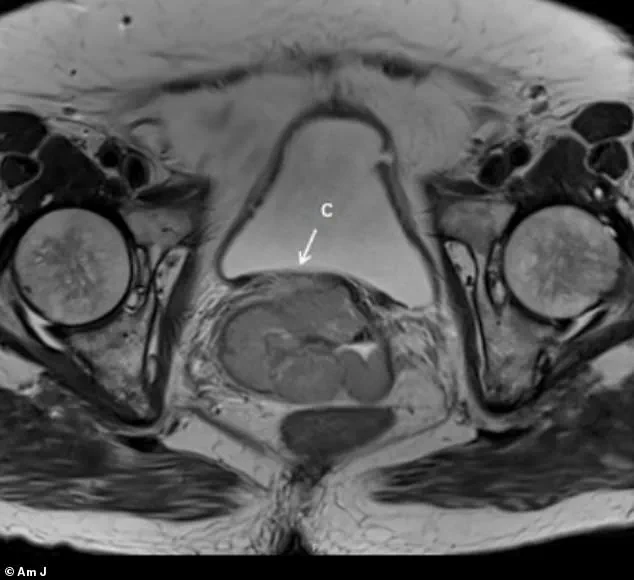

The first case involved a patient whose condition was initially identified through imaging that revealed a cervical mass measuring approximately 7cm and a pelvic mass measuring 2cm.

An MRI, shared under strict confidentiality protocols, showed a cervical mass measuring 7.8cm by 5.7cm by 1.0cm, extending into the lower third of the vagina.

A pelvic examination uncovered a cervical mass nearly 8cm by 6cm by 1cm in the vaginal wall, which again exhibited the pigmented appearance characteristic of melanoma.